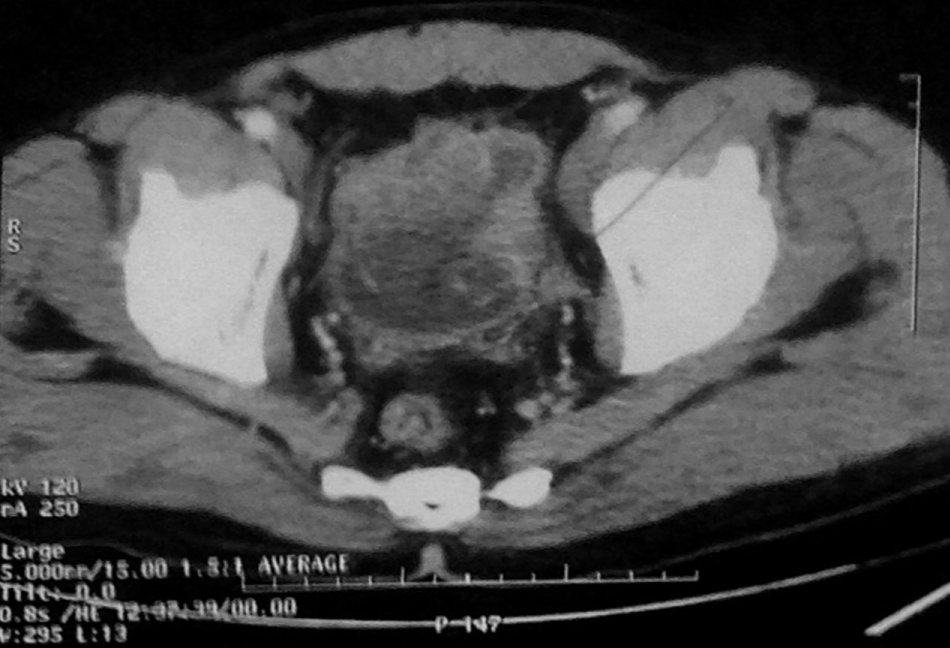

The composite specimen of urinary bladder, prostate with seminal vesicles, both sided ureters and perivesical adipose tissue measured 10 × 8 × 5.5 cm. On cutting, the urinary bladder showed a mass measuring 5 cm in its greatest dimensions (Figure 2). Sections from the representative areas on microscopy showed sheets and nests of loosely cohesive, small round to oval cells with hyperchromatic coarsely granular nuclear chromatin and scant cytoplasm (Figure 3).

Figure 3: HES. Sheets and nests of loosely cohesive, small round to oval cells with Scant cytoplasm. View Figure 3

Mitotic figures and nerve invasion were frequent. Tumor invaded complete wall of urinary bladder, the prostatic parenchyma and the seminal vesicles. The neoplastic cells on immunohistochemistry exhibited Chromogranin A and focal cytokeratin positivity and were negative for synaptophysin and CD56.

Histologically, in 68% of cases, the SCC coexists with classic the urothelial carcinomas or adenocarcinomas of the bladder. Our case was diagnosed as pure SCC. Microscopic examination reveals a tumor composed of sheets and nests of loosely cohesive, small, round, or oval cells with very scanty cytoplasm. The tumor cell nuclei are hyperchromatic with coarsely granular chromatin. Nuclear molding can be seen. Mitotic figures are present and may be frequent. Nucleoli are absent or small. Tumor necrosis is often present. The urinary cytology shows often single and loosely cohesive clusters of tumor cells with typical SCC morphology. Neuroendocrine markers, such as chromogranin A, synaptophysin, CD56, and neuron specific enolase (NSE), are often focally or diffusely positive for these tumors by immunohistochemical methods, and they are useful tools that aid in establishing the diagnosis. A cocktail of cytokeratin (CK) markers is often nonreactive, but low molecular cytokeratin, CAM5-2, and epithelial membrane antigen (EMA) are mostly positive [4].